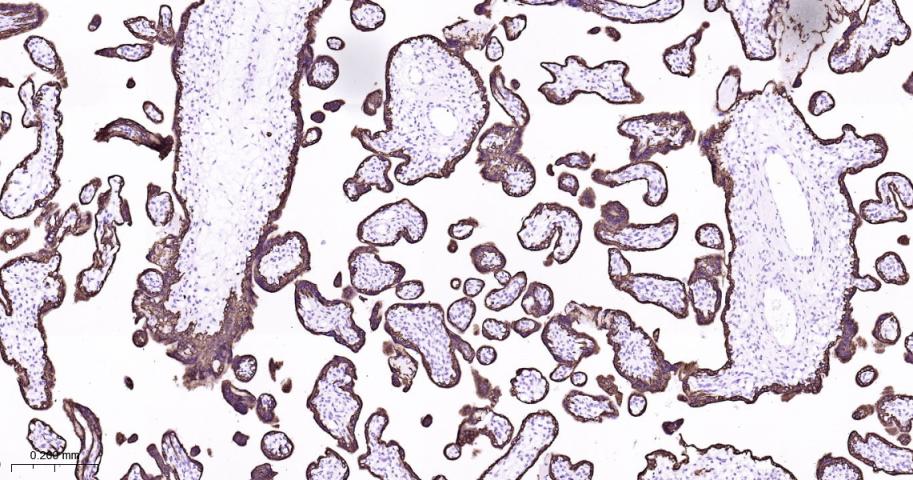

Paraformaldehyde-fixed, paraffin embedded Human placenta; Antigen retrieval by boiling in sodium citrate buffer (pH6.0) for 15 min; Antibody incubation with Keratin 7 Monoclonal Antibody, Unconjugated(bsm-60218R) at 1:200 overnight at 4°C, followed by conjugation to the bs-0295G-HRP and DAB (C-0010) staining.